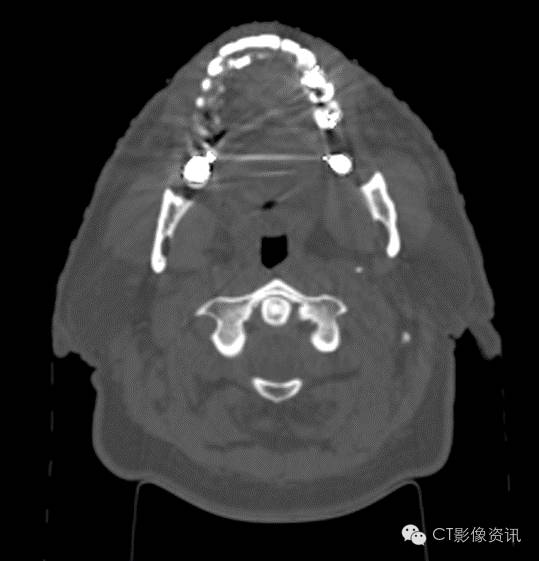

牙齿填塞物

Without MAR

With MAR

Smart MAR 有效地消除了牙齿填充物导致的伪影,周边清晰,利于观察。